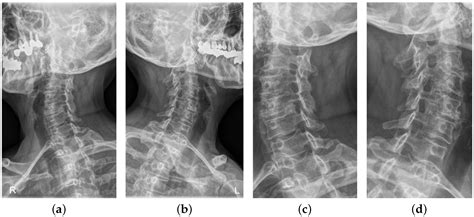

To confirm whether you have spinal narrowing neck, a healthcare professional will typically conduct a thorough physical examination followed by imaging studies. Because clinical symptoms can mimic other conditions, such as peripheral neuropathy or rotator cuff injuries, accurate diagnostics are essential.

X-Ray Identifies bone spurs and alignment issues.